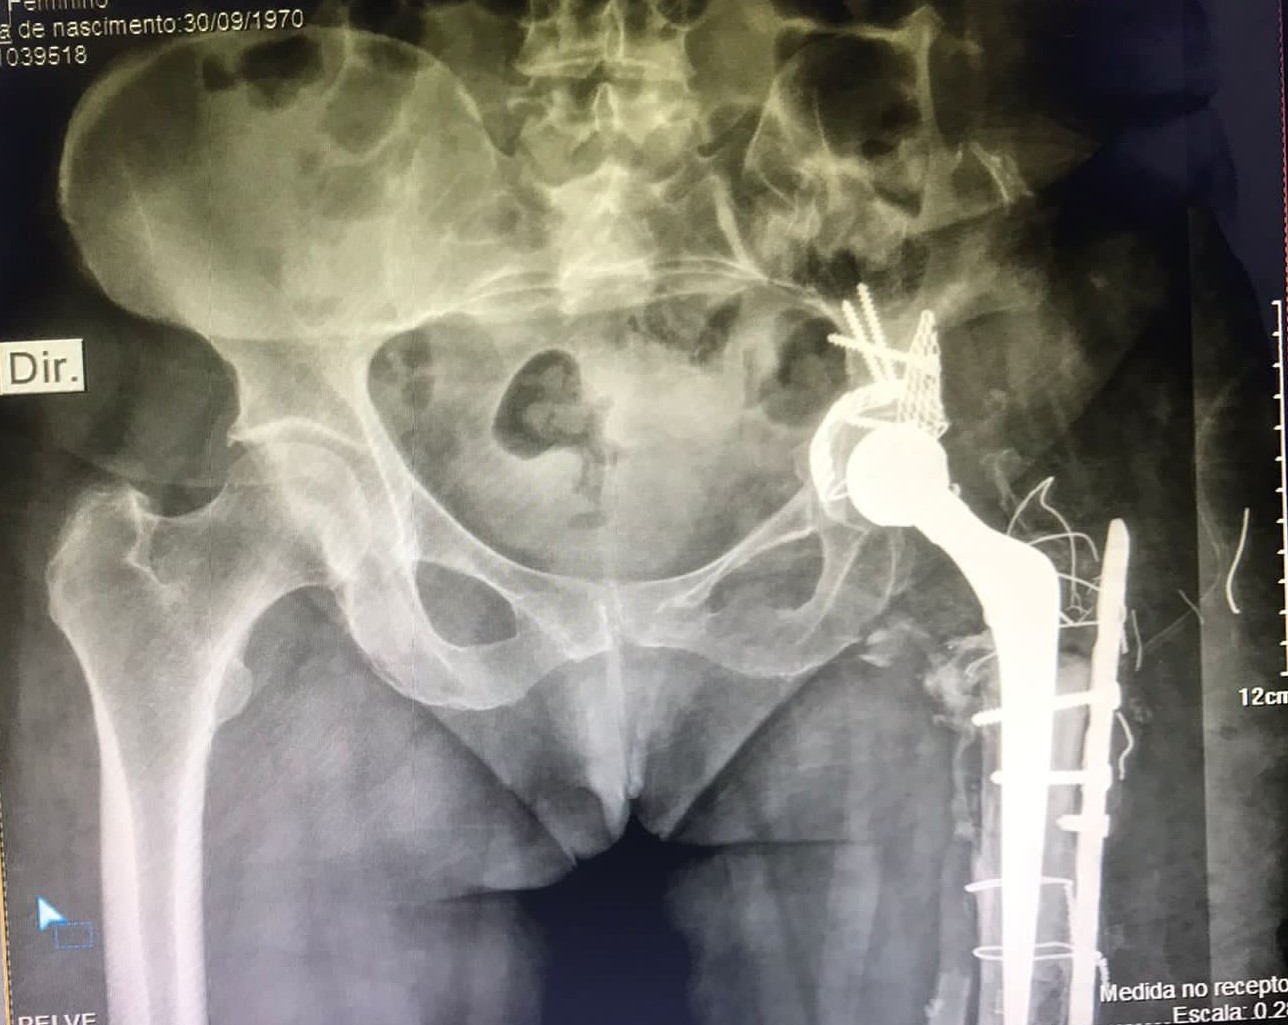

• Próteses de Quadril (Primárias  e Revisões);

• Cirurgia do Quadril;